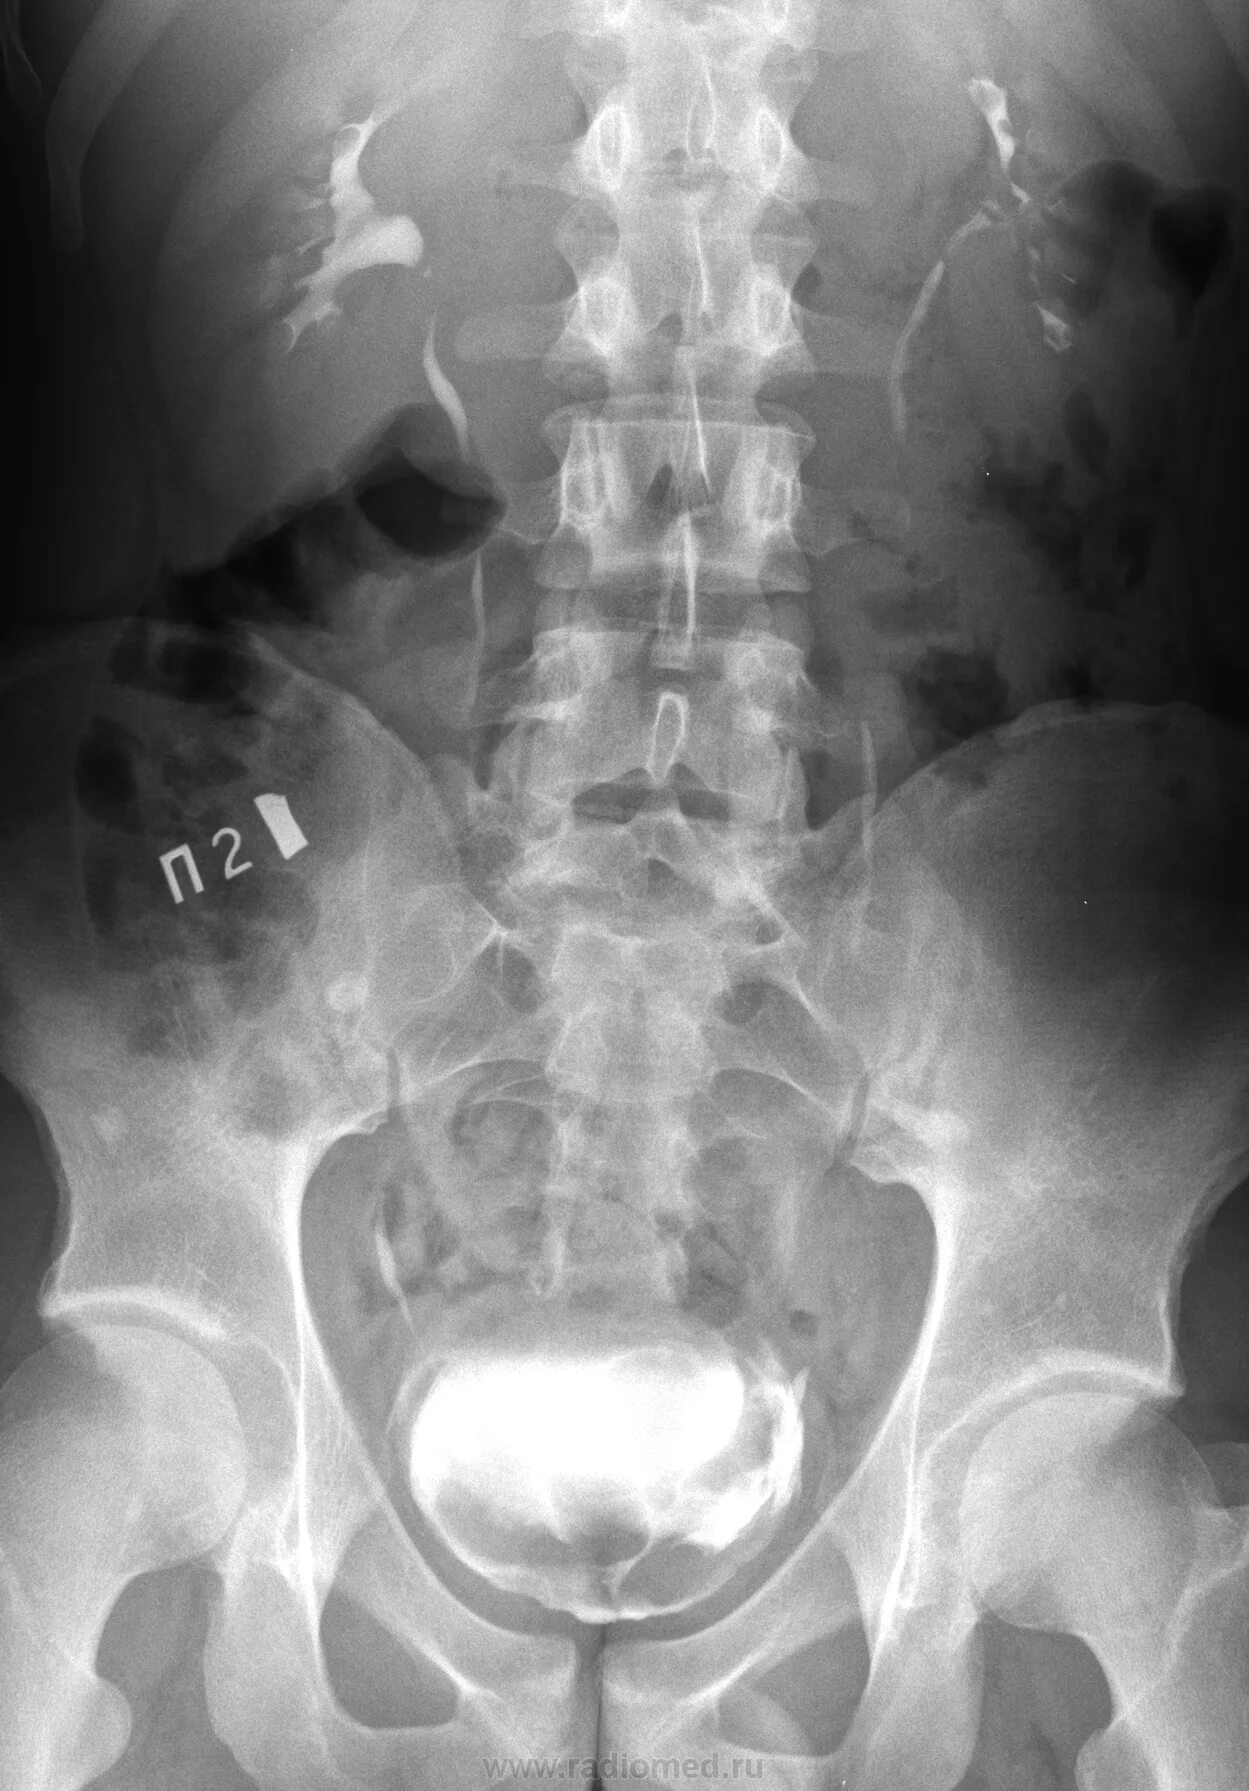

Урография с контрастом